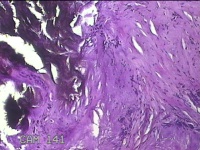

左外踝包块

性别

男

年龄

31岁

临床诊断

皮下结节

一般病史

发现左外踝包块1年余。

标本名称

大体所见

灰白暗红色包块1.8x1.3x0.7cm一个,表面糜烂,切开包块,内见大量石灰样物,内壁粗糙。

去了解病史,应该是痛风结节。